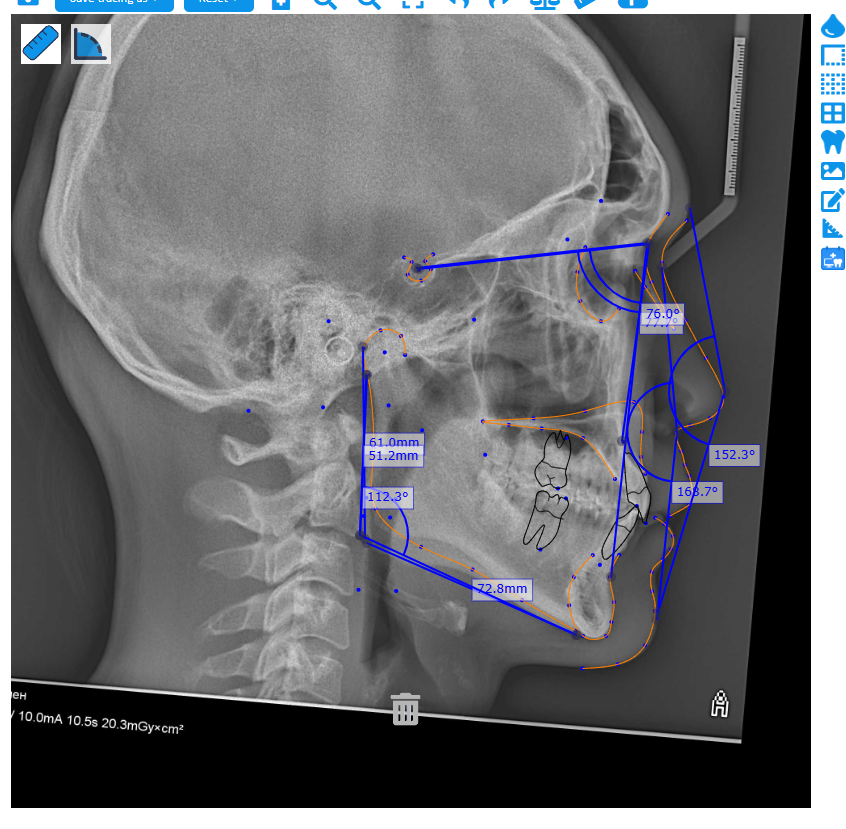

CCW+Lefort I + genio + BSSO(??). Like default trimax or not? What u think?

lefort for sureView attachment 4652888Planning maxilla, SNA too low, genio for better mentolobial angle. And u can see I have too visible nasolobial folds that makes me aged af. Local surgeon said I’m class I.

CCW+Lefort I + genio + BSSO(??). Like default trimax or not? What u think?